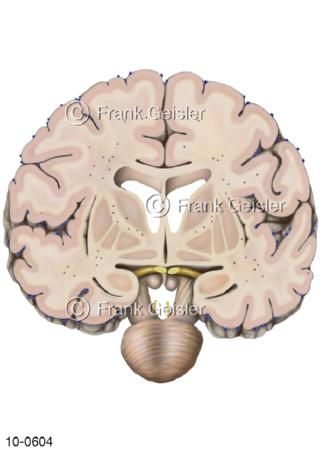

Bildergalerie Nervensystem

Bilder zum Nervensystem,dem Gehirn, Teil des zentralen Nervensystem, Zentralnervensystem ZNSmit Rückenmark, Abbildungen zum Nervengeflecht (Nervenplexus), die Verflechtungen von Nervenfasern, aus der Wirbelsäule hervortretende Nervenäst sowie Nervenzellen der Nerven